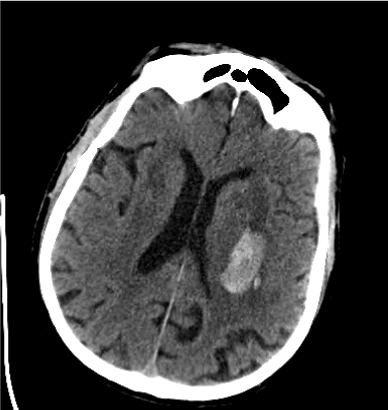

We explored the effects of INR on the volume changes. Assuming similar baseline volume and similar time since baseline CT, every 1 point increase in INR was associated with a median increase of 2.36 ml (95% CI 0.46 – 4.26, p= 0.024) in hematoma expansion measured as the change from baseline in volume (Figure 1-4). Given the imbalance in proportion of hypertension, pre-admission mRS, GCS and age between the included and excluded groups, we investigated the effect of INR adjusted for the variables by inclusion in the median regression model in addition to other covariates, the association between INR and hematoma growth remained significant with an effect size of 1.92 ml (95% CI 0.46- 3.37, p=0.01) (Table 3).

Figure 1. First CT Scan of the Patient with Lower INR Value (INR1.0)

Figure 2. Second CT Scan of the Patient with Lower INR Value (INR1.0)